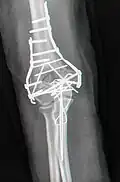

Bei Erwachsenen bedeuten perkondyläre Frakturen, dass die Trochlea humeri mit den Epikondylen nicht nur vom Schaft getrennt, sondern auch in sich, in zwei oder mehr Teile, gebrochen ist. Die operative Versorgung ist aufwändig: Der Nervus ulnaris muss freigelegt, das Olecranon durchsägt und mit dem Musculus triceps brachii hochgeklappt werden. Wie ein dreidimensionales Puzzle wird die Kondylenrolle rekonstruiert und mit Kirschner-Drähten und Kleinfragment-Lochschrauben zusammengehalten. Mit Drittelrohr- oder Rekonstruktionsplatten an beiden Seiten wird die (übungsstabile) Verbindung zum Schaft wiederhergestellt. Gut geeignet, aber teuer sind anatomisch vorgeformte winkelstabile Platten (Mayo). Das Olecranon wird mit einer Zuggurtung refixiert. In Hinblick auf die komplexe Anatomie des unteren Humerusendes sollte man sich bei der Rekonstruktion ein Humerusmodell zur Seite legen.